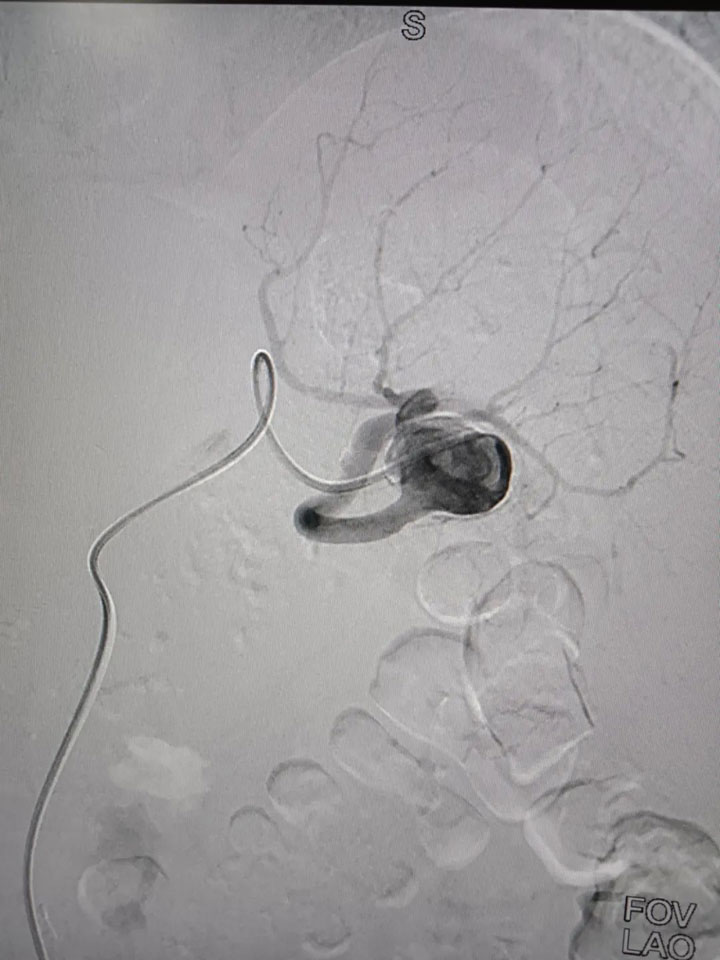

经过完善的术前评估,普外科邀请集团普外医疗中心血管外科桂锐主任、胡玉东主任,仅在股动脉做一2cm小切口,通过一根导丝,精准定位瘤体位置,将弹簧圈置入瘤腔,顺利完成手术。

“患者的脾动脉瘤直径较大,属于囊状动脉瘤,瘤体向动脉一侧偏心性扩张,这类口袋状的动脉瘤,破裂的风险更高,占总数的75%。患者发现及时,手术顺利,很幸运。”胡玉东主任说。